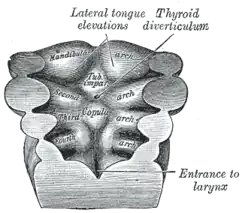

Desenvolvimento

No desenvolvimento do embrião, com 3-4 semanas de idade gestacional, a glândula tireoide aparece como uma proliferação epitelial no assoalho da faringe, na base da língua, entre o tubérculo impar e a cópula língua. A cópula logo fica coberta pela eminência hipofaríngea[18] em um ponto posteriormente indicado pelo forame ceco. A tireoide então desce na frente do intestino faríngeo como um divertículo bilobado através do ducto tireoglosso. Nas semanas seguintes, ele migra para a base do pescoço, passando na frente do osso hióide. Durante a migração, a tireoide permanece conectada à língua por um canal estreito, o ducto tireoglosso. No final da quinta semana, o ducto tireoglosso degenera e, nas duas semanas seguintes, a tireoide descolada migra para sua posição final.[18]

As células neuroendócrinas parafoliculares, também conhecidas como células C, responsáveis pela produção de calcitonina, são derivadas do endoderma do intestino anterior. Essa parte da tireoide então se forma primeiro como o corpo ultimofaríngeo, que começa na quarta bolsa faríngea ventral e se junta à glândula tireoide primordial durante sua descida até sua localização final.[23]